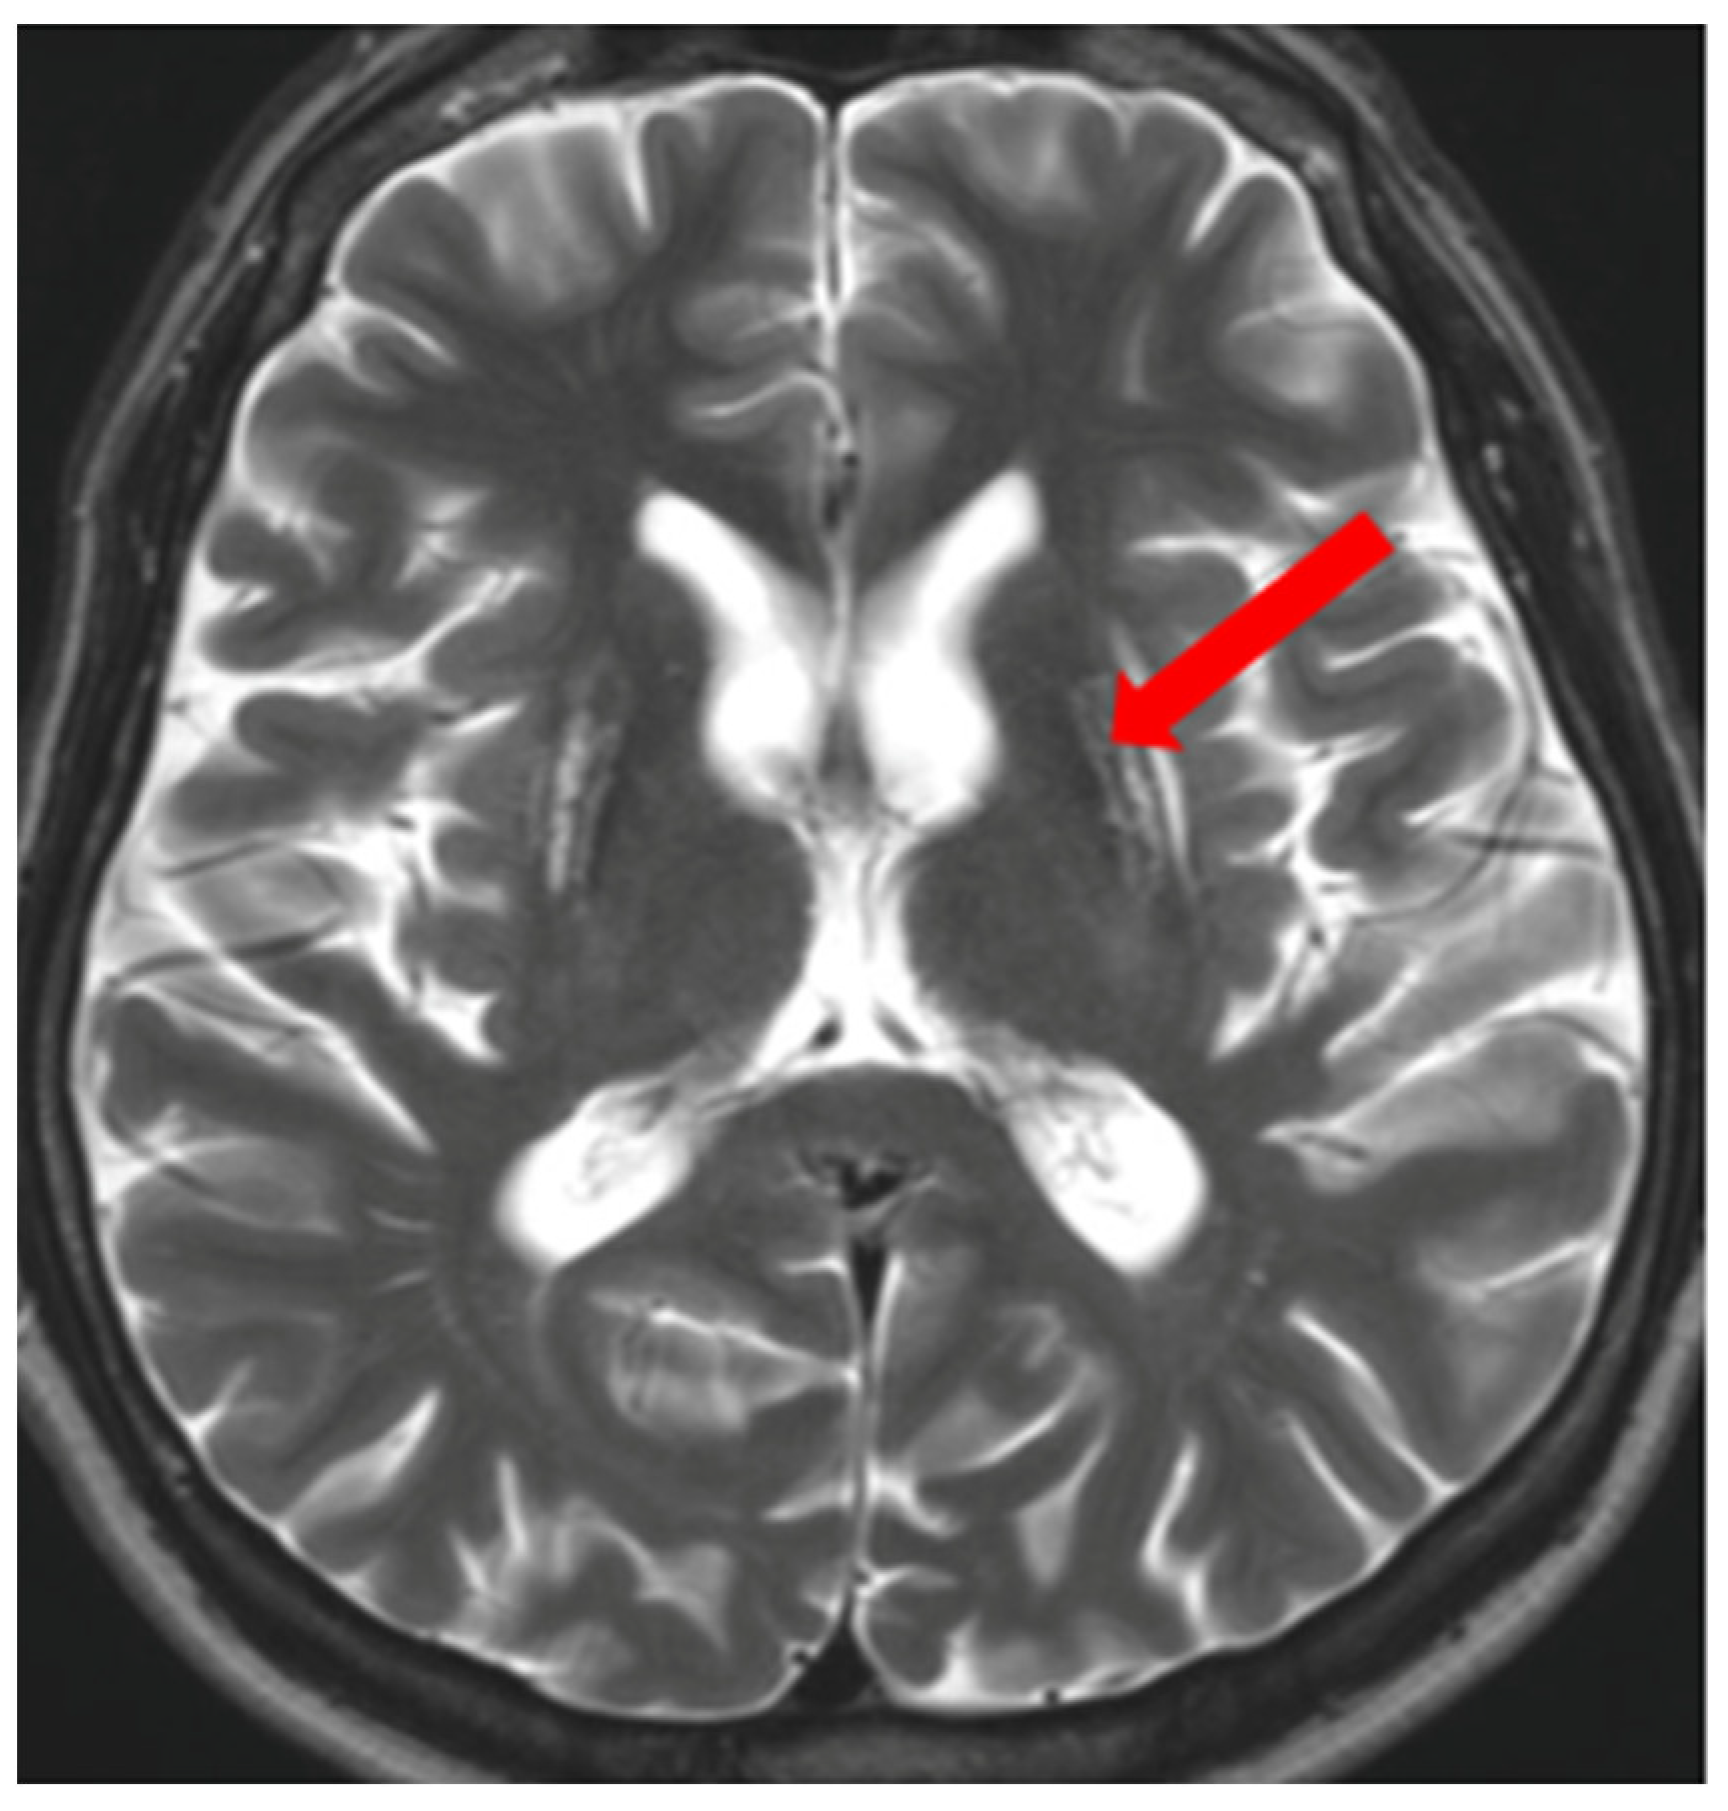

5. Neuroradiological Pathognomonic Signs of WD

- Sener, R.N. The claustrum on MRI: Normal anatomy, and the bright claustrum as a new sign in Wilson’s disease. Pediatr. Radiol. 1993, 23, 594–596. [Google Scholar] [CrossRef] [PubMed]